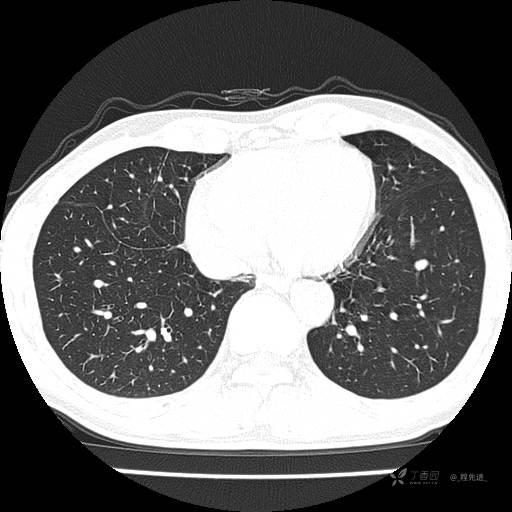

2月特别精彩病例|咳嗽、咳痰20余天,典型病例分享【结果已公布】

患者年龄:51岁

主诉:咳嗽、咳痰20余天

简要病史:20余天前开始出现咳嗽、咳痰症状,阵发性刺激性咳,白色粘痰,不易咳出,无发热,无咯血,无恶心、呕吐等不适,未诊治,咳嗽、咳痰症状持续存在。

体格检查:T:36.3 ℃ P:79 次/分 R:20 次/分 BP:128/64 mmHg,神志清楚,呼吸平稳,双肺呼吸音粗,右下肺闻及细湿性啰音。心率79次/分,节律整齐,各瓣膜听诊区未闻及病理性杂音。腹部未见异常,双下肢无水肿。

辅助检查:我院门诊胸部CT示:如下。心电图:窦性心律;正常心电图。